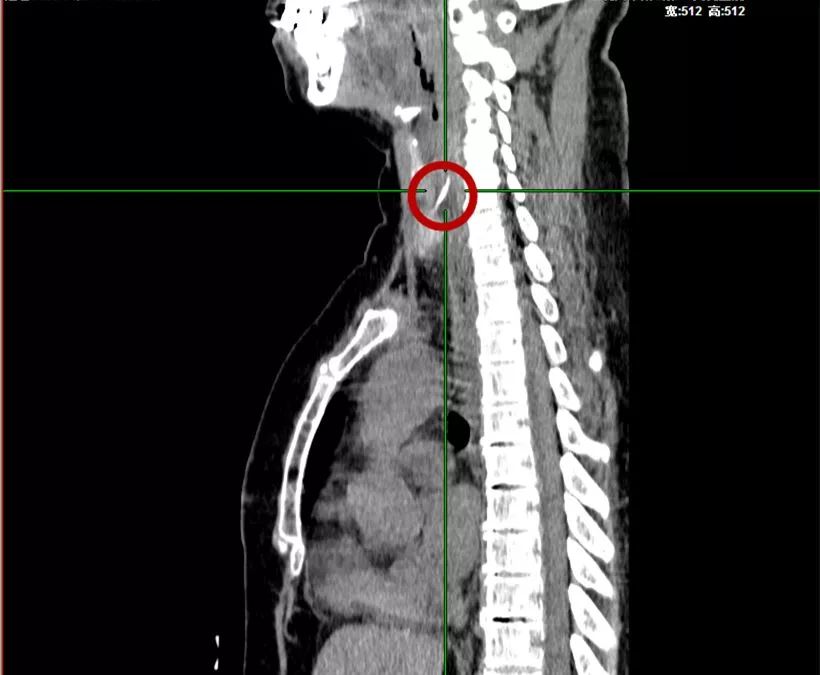

59岁的李大姐误吞鱼骨,咽痛了1天,来医院耳鼻喉科就诊。医生给她进行了常规的咽喉部检查,却并未在食管中发现鱼骨。于是赶紧给她拍了食道的CT片。可CT影像出来后,依然没有在食管内找到鱼骨的影子。

医生再次仔细阅片,发现上段食管壁左前方有一个亮点,再循着亮点往外侧软组织看去,好几个层面都有,竟然是连着的一条索状高密度影。

鱼刺

原来李大姐的鱼刺已经刺破了食管,扎进了颈部软组织及左侧甲状腺内,并且已经引起了炎症。如果不马上取出鱼刺,一方面,颈部炎症会扩散,变得难以控制,另一方面,如果鱼刺扎破颈动脉,后果不堪设想。

因为李大姐的鱼刺已经不在食管内了,医生在全麻手术下从颈部切开皮肤,终于在食管、气管和甲状腺的夹缝中找到并取出了李大姐的鱼刺。但因为李大姐的部分甲状腺已经被刺得发炎溃烂,只能切除。目前李大姐的咽痛已经缓解了,接下来还需要等食管的破口及颈部的切口愈合。